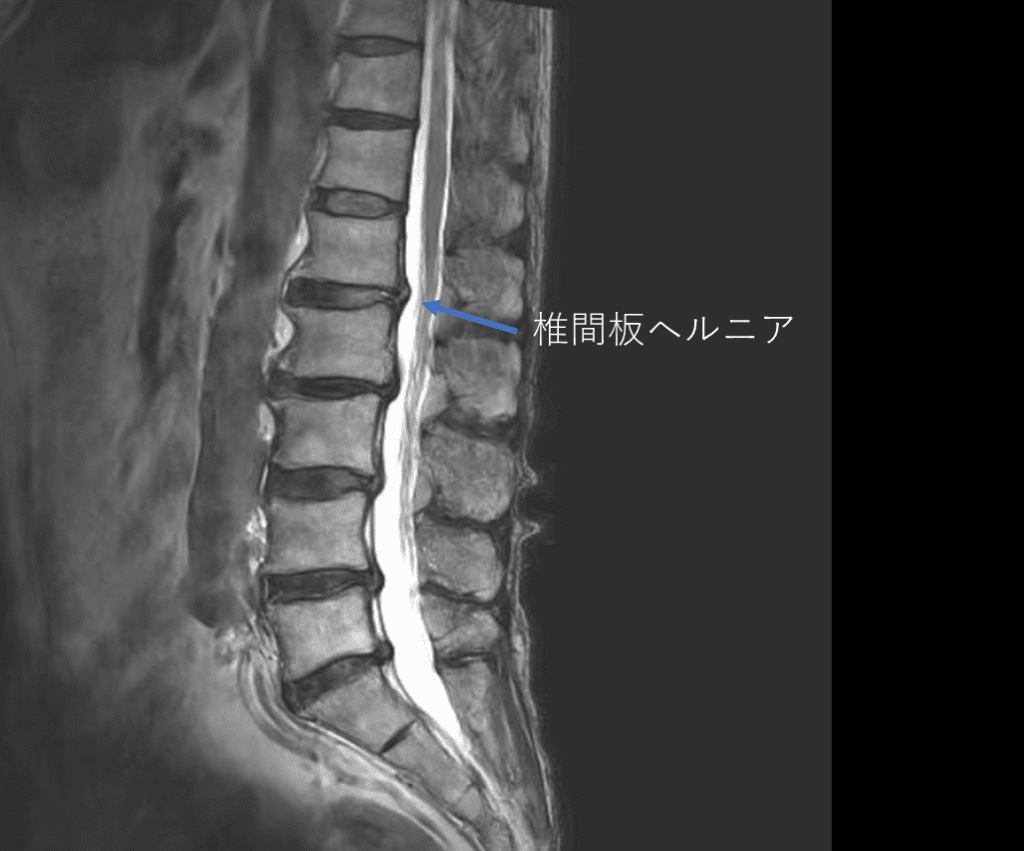

画像及び所見について

- L1/2,2/3,3/4,4/5,5/s-椎間板変性

- L1/2-椎間板ヘルニア

以上の事が画像上認められます。

・L1/2-椎間板ヘルニアを認め、主症状の原因の可能性がある

・L3/4,4/5-椎間板変性を認め、主症状の原因の可能性がある